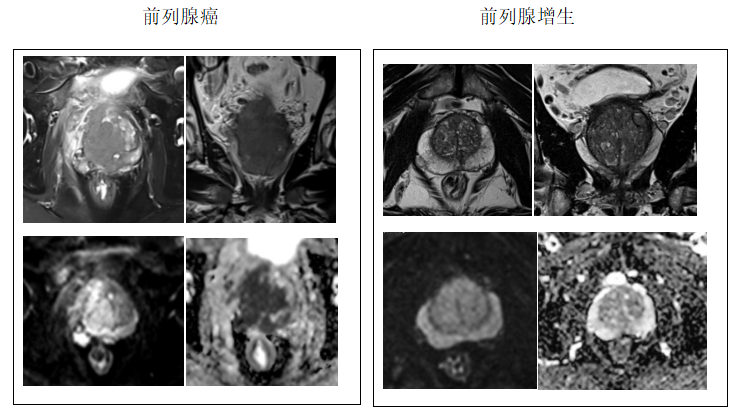

随着社会的老龄化,越来越多的老年男性出现尿急、尿频等泌尿系症状,前列腺癌的发病率逐年上升,已成为威胁中老年男性健康的主要癌症之一,前列腺癌早期常无明显症状,部分患者可能出现尿频、尿急、尿等待等临床症状,难以与前列腺良性增生鉴别。医生会让患者做前列腺磁共振检查来评估病情,但看到检查结果上的这些专业术语往往会让人感到困惑和不安。别急今天就一起来了解“前列腺磁共振PI-RADS”

(一)、前列腺磁共振(MRI)检查是现代医学评估前列腺疾病的重要手段,尤其在前列腺癌的早期筛查与诊断中发挥着关键作用。为规范前列腺磁共振影像解读,2012年,欧洲泌尿生殖放射学会首次推出了“前列腺影像报告与数据系统”(Prostate Imaging Reporting and Data System,简称PI-RADS),即常说的“PI-RADS”,旨在规范前列腺MRI报告,减少了观察者间的差异,现在已经成为指导前列腺癌诊断和治疗的重要工具。